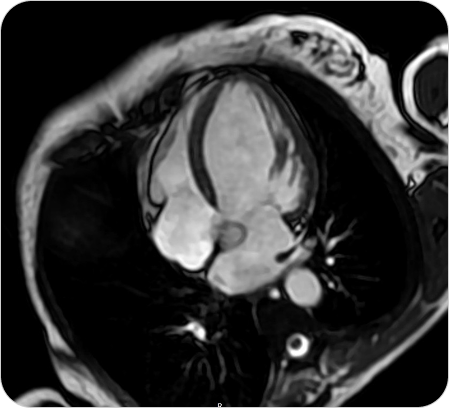

Resonancia Magnética Cardíaca

La resonancia magnética cardíaca es un estudio no invasivo y altamente especializado que permite obtener imágenes detalladas del corazón en movimiento. Brinda información precisa sobre la estructura, función, tejidos y vasos del corazón, sin utilizar radiación.

¿PARA QUE SE UTILIZA?

- Estudio de última generación para evaluar el corazón con altísima precisión, sin radiación. Diagnóstico completo de función, tejidos y circulación cardíaca.

- Evaluar la función del corazón y de las válvulas cardíacas.

Detectar infartos antiguos o recientes y analizar el daño al miocardio. - Diagnóstico de miocardiopatías (hipertrófica, dilatada, restrictiva, etc.).

- Detección de inflamación (miocarditis) o fibrosis del músculo cardíaco.

- Evaluación prequirúrgica o seguimiento de enfermedades cardíacas complejas.

- Estudio de tumores cardíacos o enfermedades congénitas.

¿POR QUÉ ES UN ESTUDIO DESTACADO?

- Estudio de última generación para evaluar el corazón con altísima precisión, sin radiación. Diagnóstico completo de función, tejidos y circulación cardíaca.

- Evaluar la función del corazón y de las válvulas cardíacas.

Detectar infartos antiguos o recientes y analizar el daño al miocardio. - Diagnóstico de miocardiopatías (hipertrófica, dilatada, restrictiva, etc.).

- Detección de inflamación (miocarditis) o fibrosis del músculo cardíaco.

- Evaluación prequirúrgica o seguimiento de enfermedades cardíacas complejas.

- Estudio de tumores cardíacos o enfermedades congénitas.

Resonancia Magnética Cardíaca

La resonancia magnética cardíaca es un estudio no invasivo y altamente especializado que permite obtener imágenes detalladas del corazón en movimiento. Brinda información precisa sobre la estructura, función, tejidos y vasos del corazón, sin utilizar radiación.

¿PARA QUE SE UTILIZA?

- Estudio de última generación para evaluar el corazón con altísima precisión, sin radiación. Diagnóstico completo de función, tejidos y circulación cardíaca.

- Evaluar la función del corazón y de las válvulas cardíacas.

Detectar infartos antiguos o recientes y analizar el daño al miocardio. - Diagnóstico de miocardiopatías (hipertrófica, dilatada, restrictiva, etc.).

- Detección de inflamación (miocarditis) o fibrosis del músculo cardíaco.

- Evaluación prequirúrgica o seguimiento de enfermedades cardíacas complejas.

- Estudio de tumores cardíacos o enfermedades congénitas.

¿POR QUÉ ES UN ESTUDIO DESTACADO?

- Estudio de última generación para evaluar el corazón con altísima precisión, sin radiación. Diagnóstico completo de función, tejidos y circulación cardíaca.

- Evaluar la función del corazón y de las válvulas cardíacas.

Detectar infartos antiguos o recientes y analizar el daño al miocardio. - Diagnóstico de miocardiopatías (hipertrófica, dilatada, restrictiva, etc.).

- Detección de inflamación (miocarditis) o fibrosis del músculo cardíaco.

- Evaluación prequirúrgica o seguimiento de enfermedades cardíacas complejas.

- Estudio de tumores cardíacos o enfermedades congénitas.